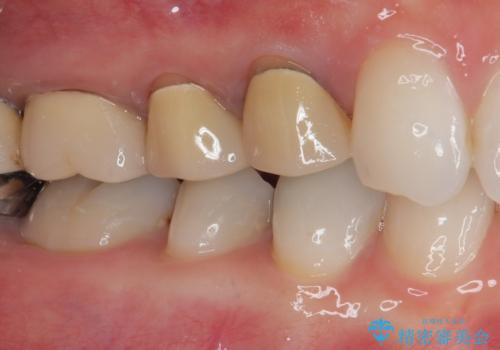

- 前歯の変色と、以前装着したクラウンが黄ばんできたことを気にして来院された患者様です。

前歯に変色が起こる場合、神経組織の失活により引き起こる可能性が高いため、診察を行ったところ、根尖部の病変や叩いたときの痛みなどが認められました。

まずは根管治療を行い、痛みの消退を確認してからオールセラミッククラウンによる補綴治療を行うこととしました。

黄ばんできてしまった小臼歯部のクラウンは、根尖部に症状を認めないため、そのままオールセラミッククラウンによる補綴治療を行うこととしました。

色がやや白いと感じましたが、ご自身でホームホワイトニングをされているそうで、今後周辺の歯を白くしていくとのことでした。